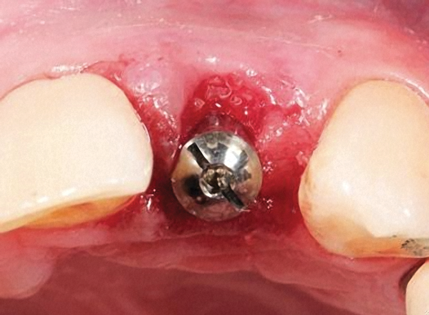

Fig 12. A healing abutment is placed and the buccal gap filled with bone graft material.

Figure 12

Fig 13. The healing abutment is removed.

Figure 13